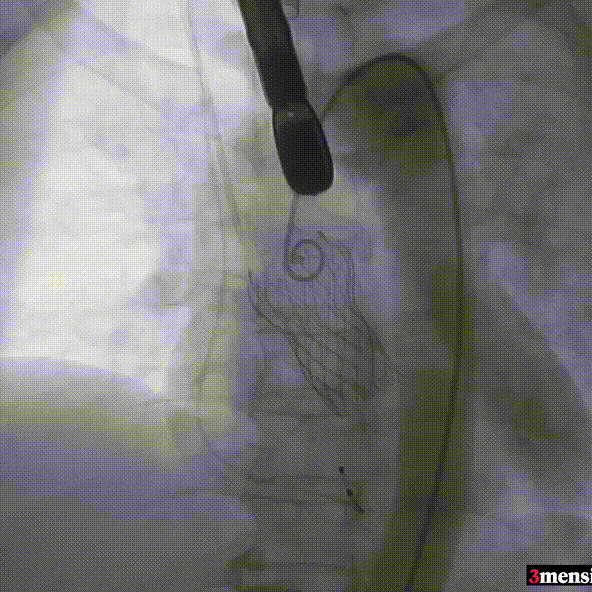

手术过程回顾:

患者全麻后,右侧股动脉建立主入路,主动脉根部造影显示主动脉瓣无明显钙化。心室内轻中量反流,主动脉及心脏情况整体较为稳定,根据术前策略预装23mm瓣膜。超硬置入左心室后,因超硬压迫无冠瓣叶导致急性反流,病人血压降至40mmHg,遂迅速将输送器送入主动脉根部,快速释放瓣膜后,病人血压恢复至正常。瓣膜脱钩后造影显示左冠开口存在一定狭窄,IVUS评估左冠开口狭窄约60%,符合PCI指征,植入开窗支架改善狭窄,最终再次造影加IVUS评估左冠开口,确定狭窄解除。

主动脉根部造影

输送器定位